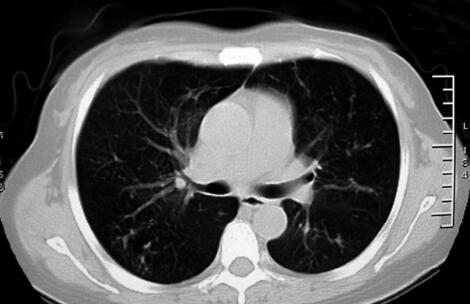

治疗1周后,患者体温恢复正常,气短较前好转,肺部干鸣音消失,仍可闻及散在湿啰音,胸部CT示胸腔积液吸收,斑片影无明显变化(图3)。治疗1个月后,患者无临床症状,复查血常规正常;复查胸部CT示双肺斑片影较前明显吸收(图4)。

图4